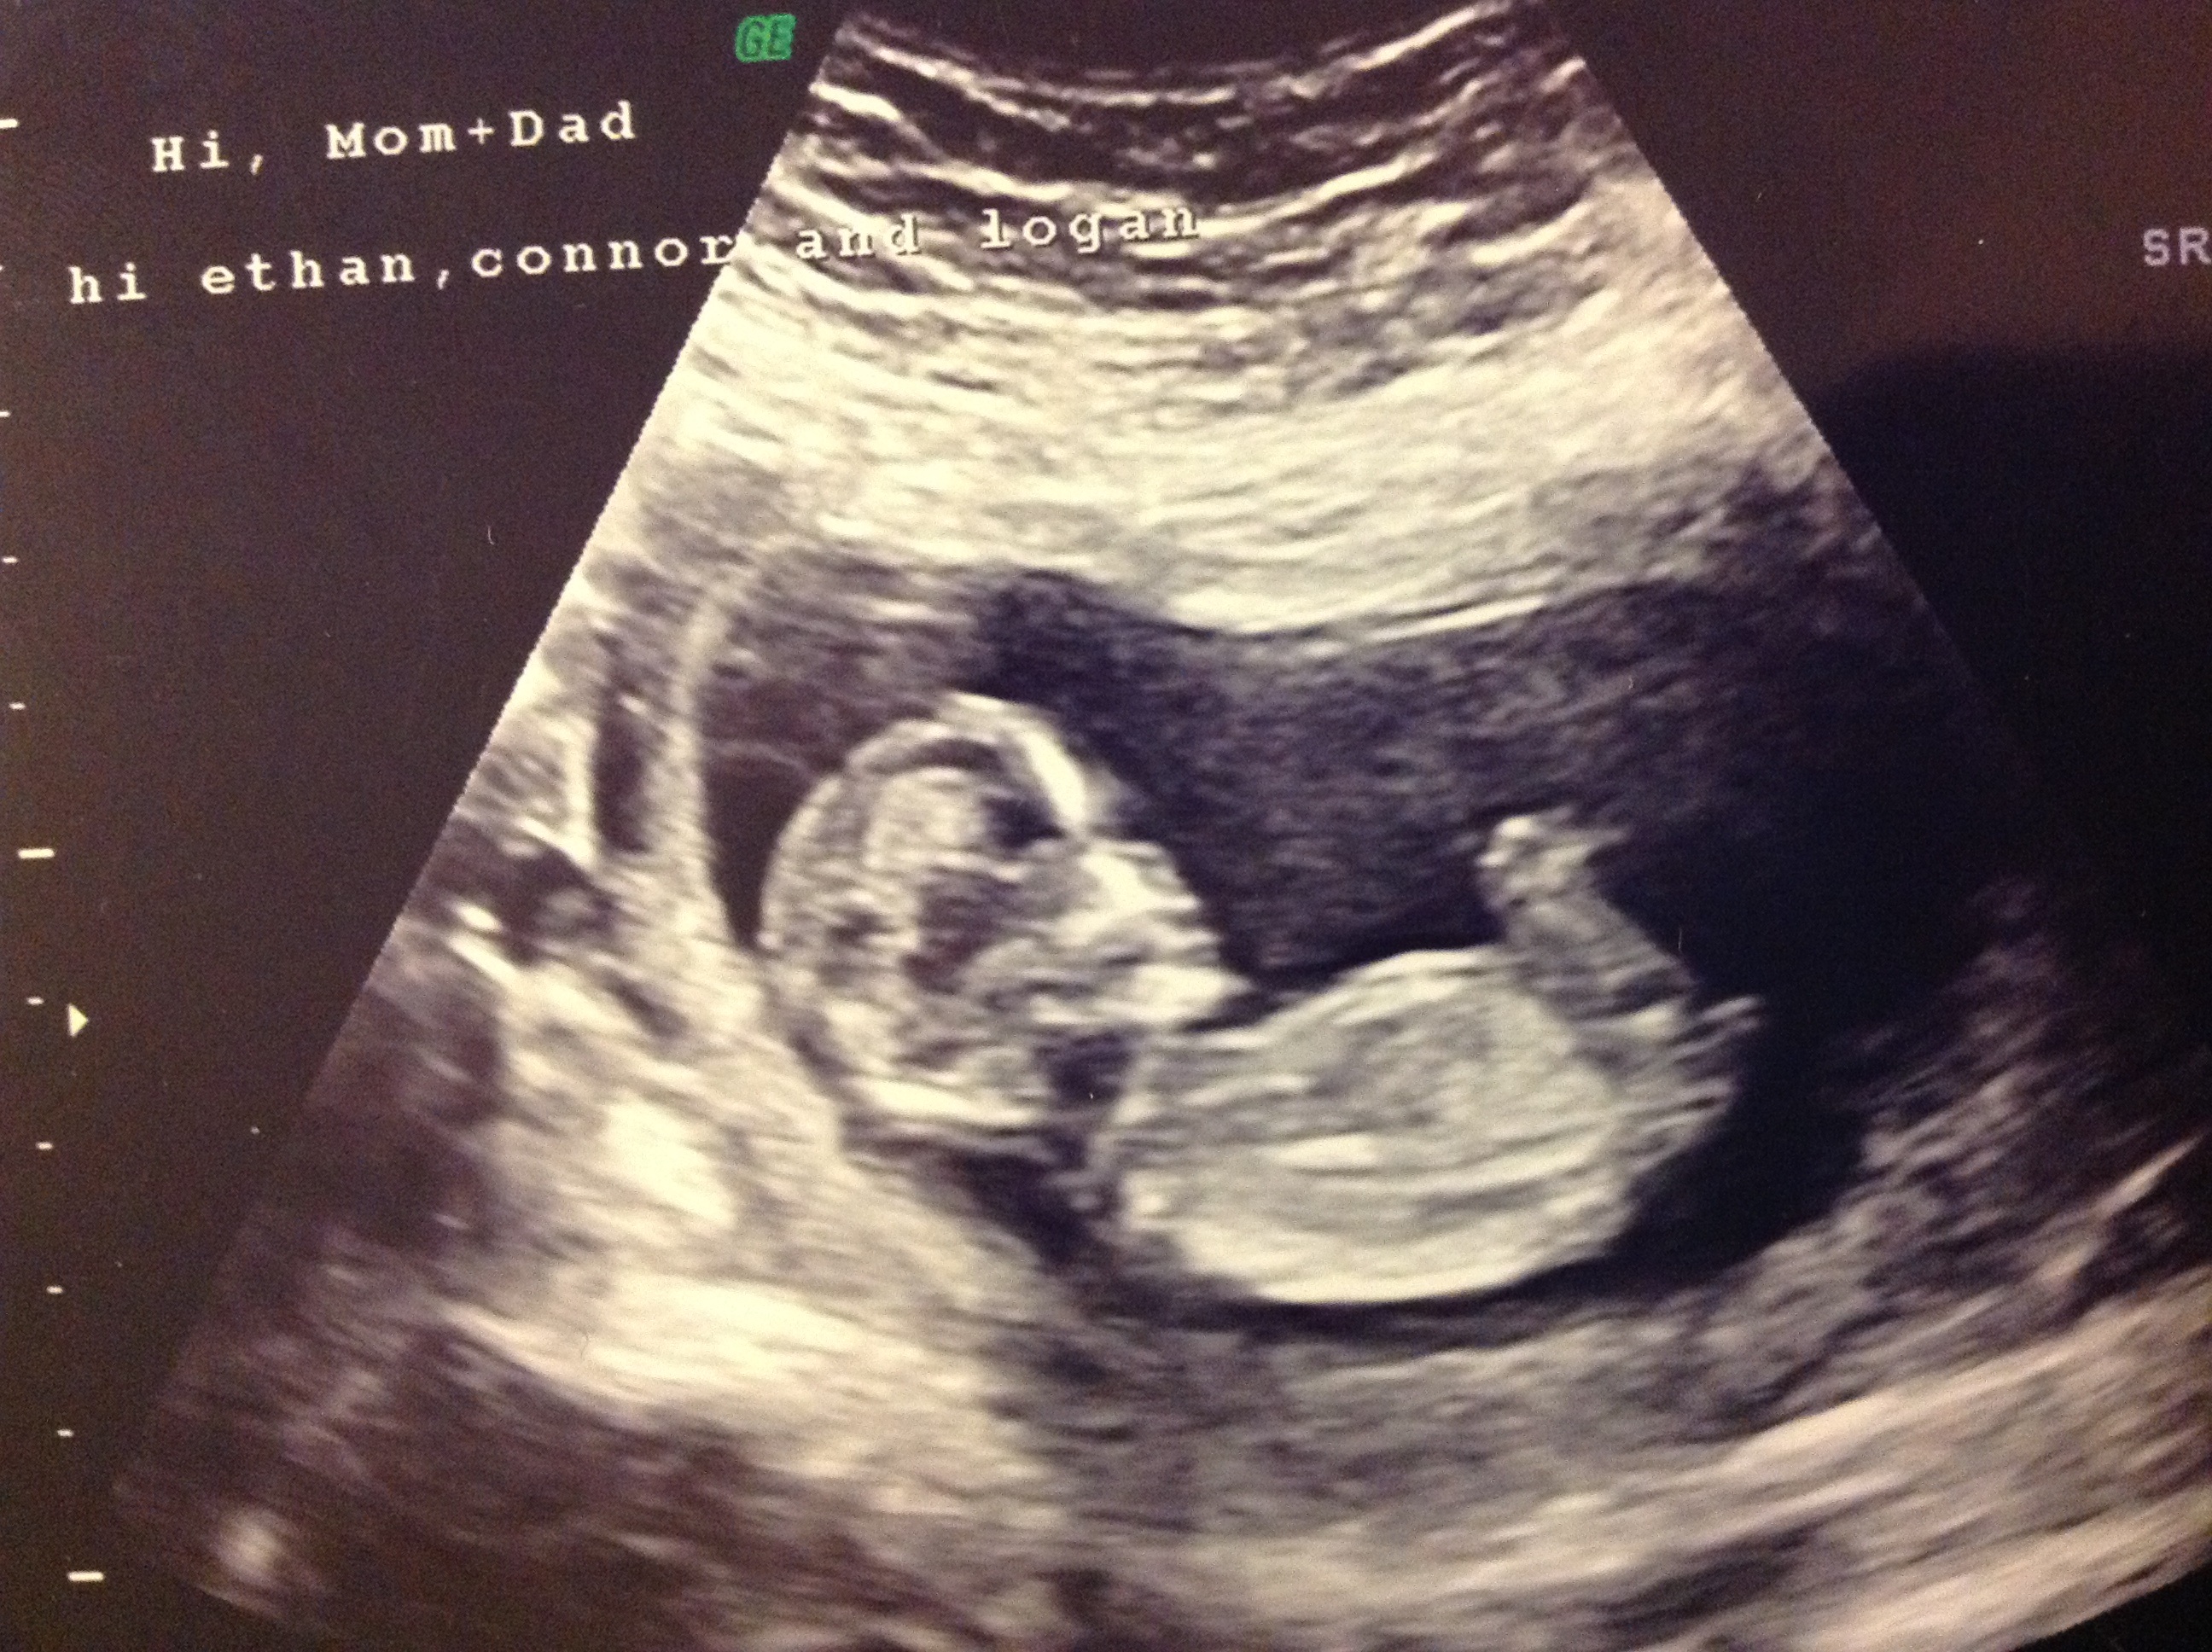

Curious if anyone sees a nub. The tech saw something at a different angle that looked like a nub but was sticking straight up, no angle. Then later she said it looked parallel and she wasn't sure. She isn't very experienced with the nub theory. Just wondered if this pic is at a good angle to be ale to guess, not sure if I'm seeing a nub or if it's something else. Thanks! Attachment 7709Attachment 7709